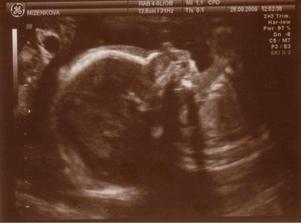

16.7.09: 13tt+6 veškeré testy v pořádku, vit. a minerály se nám spravují, krásně vidět celá páteř, srdíčko i žaludek. Jen byl celou dobu zády takže z focení nic nebylo ☹ mezi nohama mělo pupeční šňůru a tak nás s tatínkem nechává pořád v nejistotě co že je to za štěstíčko 🙂